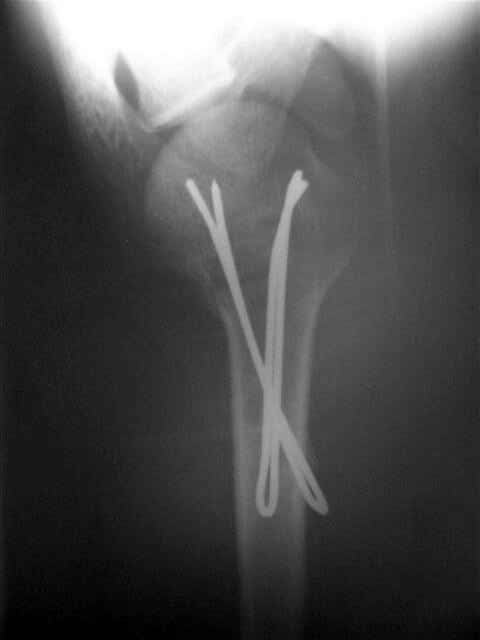

Клинические снимки - 3 недели после операции

Посылаю послеоперационные Рг граммы.

Поздравляю, получилось просто замечательно. Если можно, расскажи чуть подробнее, как делали - как вправляли, как вводили спицы, поворачивали ли их?

Спасибо за поздравления:-))

Я и сам доволен результатом. В предпоследнем письме я кратко описал ход операции - закрыто репонировать не удалось( 2 недели с момента травмы и 1 неделя после неудачной репозиции) после удаления пучков спиц, пришлось сделать - 2см разрез на уровне перелома и с помощью периостального элеватора (золотое правило механики) *одеть* головку на дистальный отломок.

Спицы проводил через старые отверстия, вращая пучок импактором- направителем при его введении в головку.